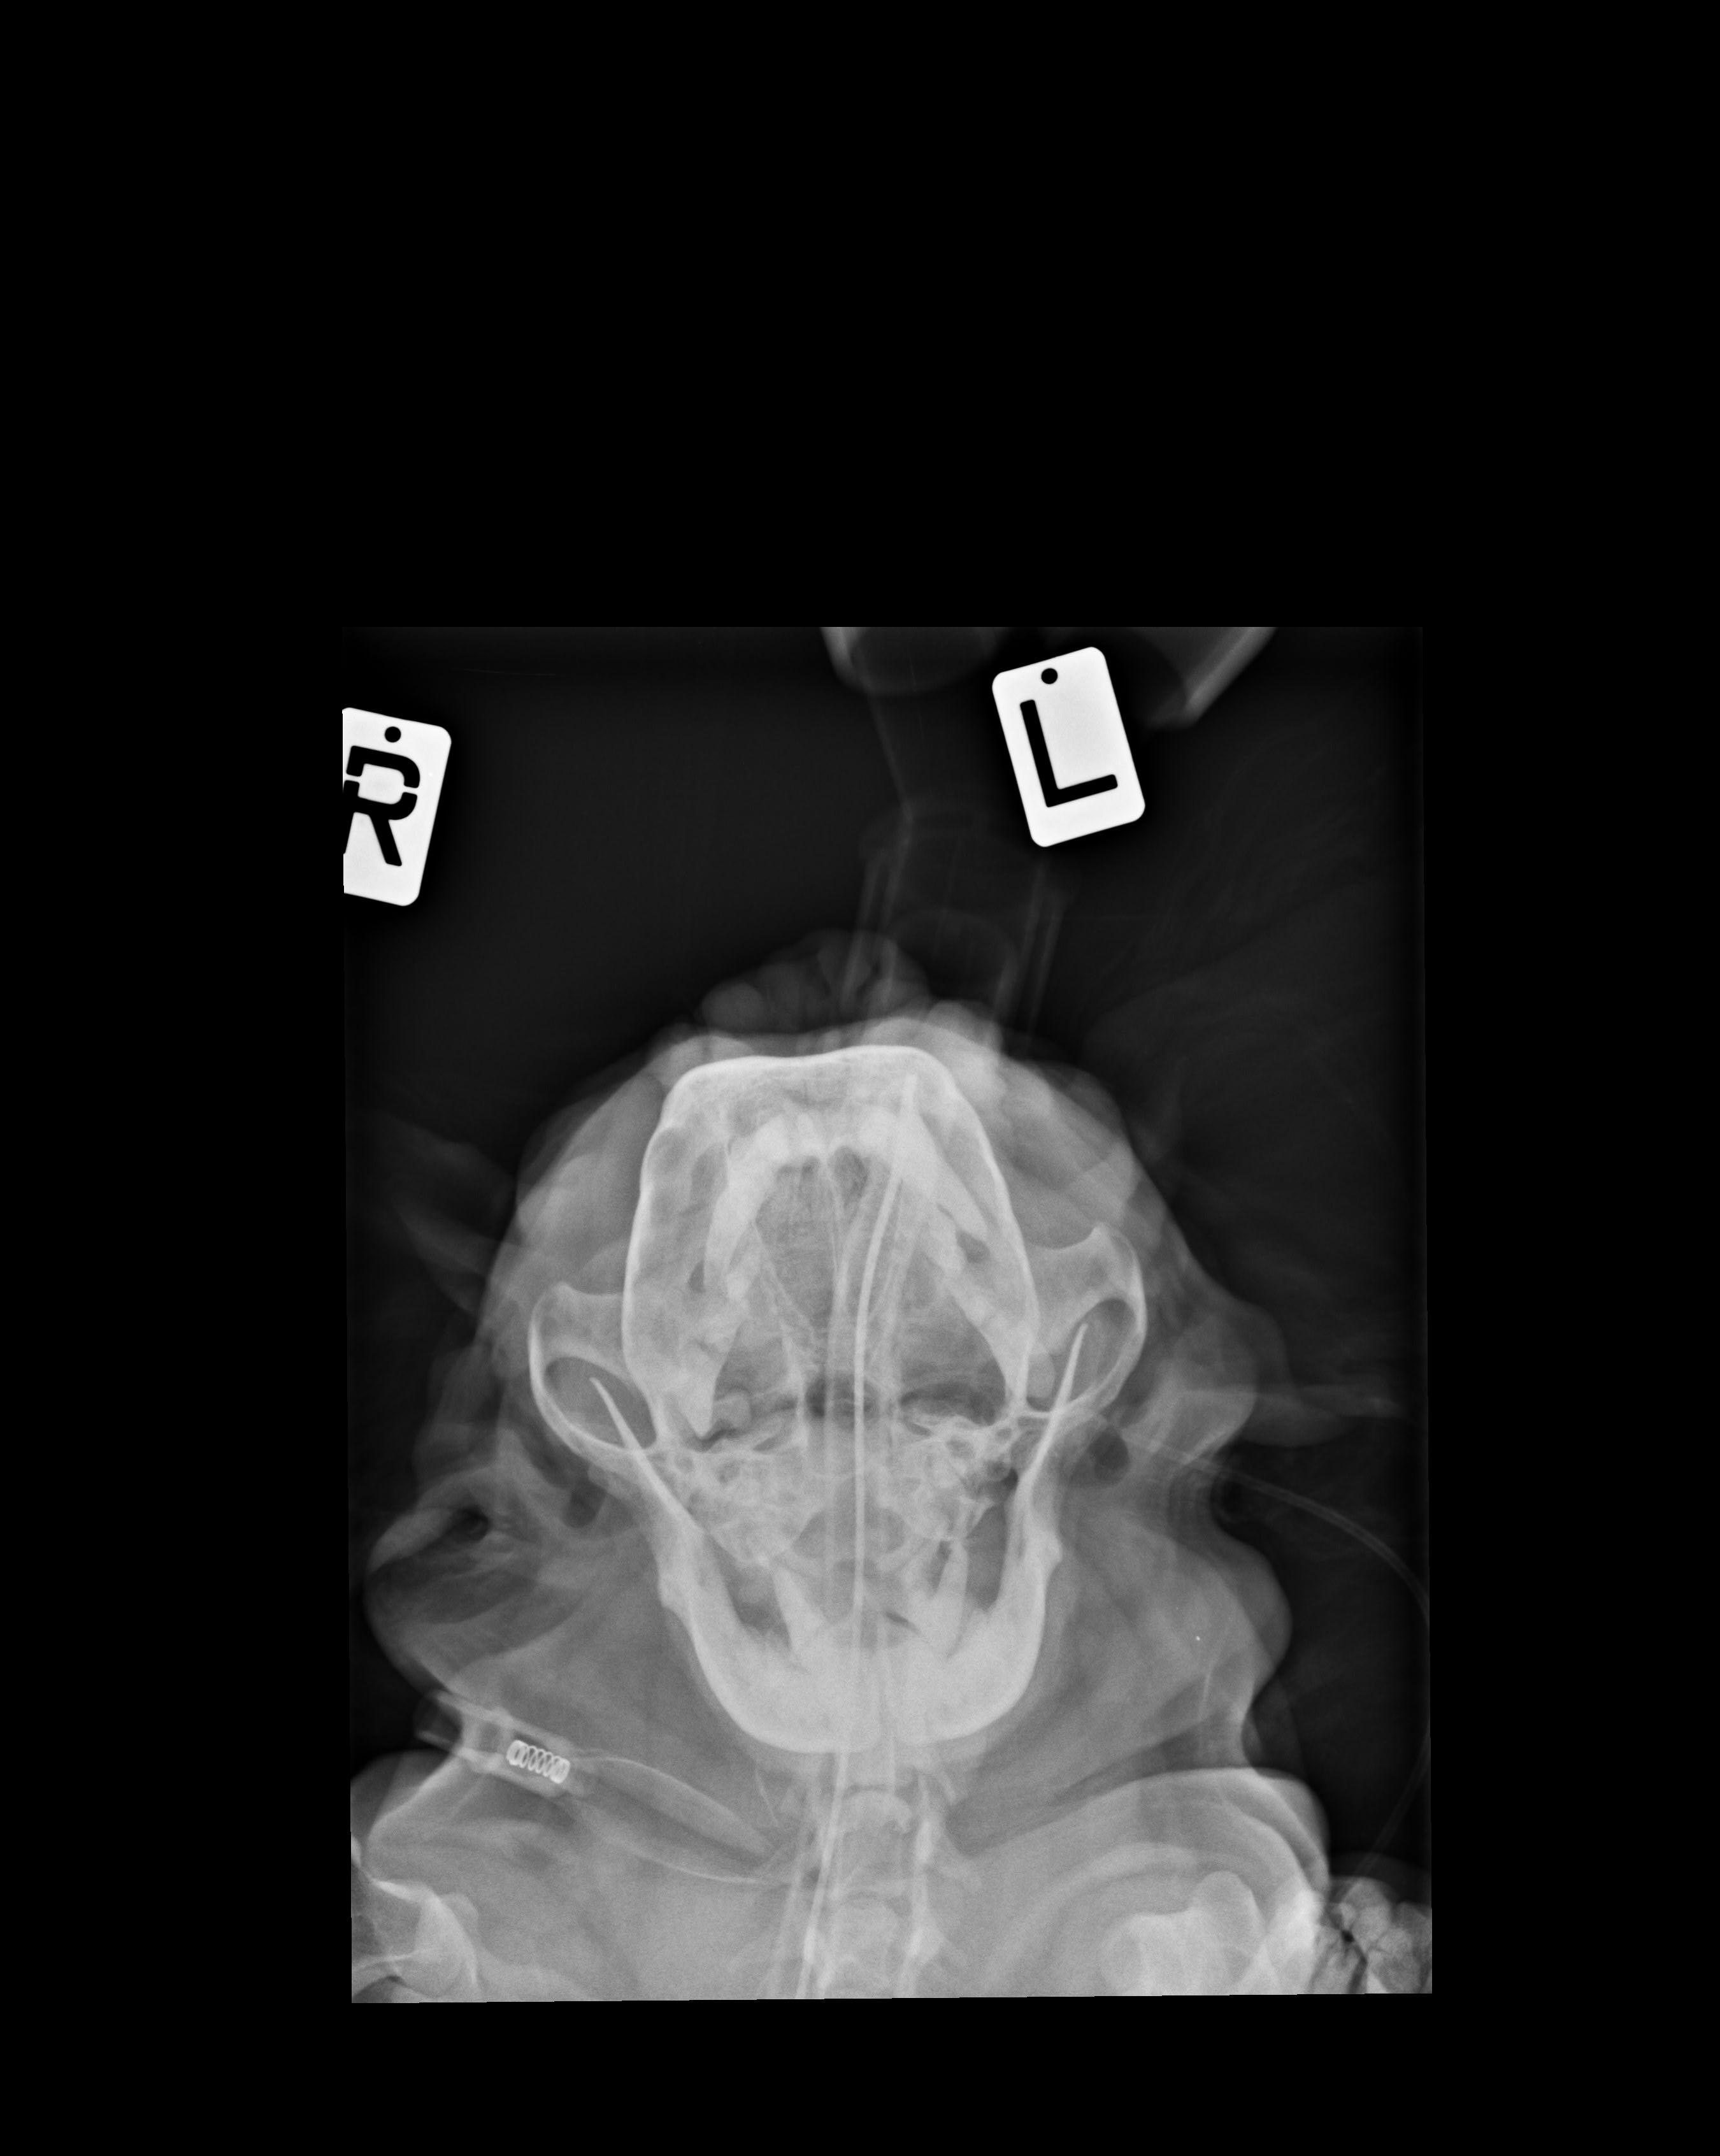

My dog (Cavalier) is showing signs of loss of hearing. She can no longer hear me when I call her from a distance. My vet has diagnosed "glue ear" and recommending myringotomy in both ears. Is this necessary or even advisable?

This is unfortunately not uncommon in Cavaliers and yes a myringotomy is an appropriate treatment. You could pursue more advanced imaging (a CT or MRI) before surgery to get more comfortable that it's required in Layla's particular case. Here is some more general info about "glue ear" https://www.vetinfo.com/glue-ear-in-dogs.html